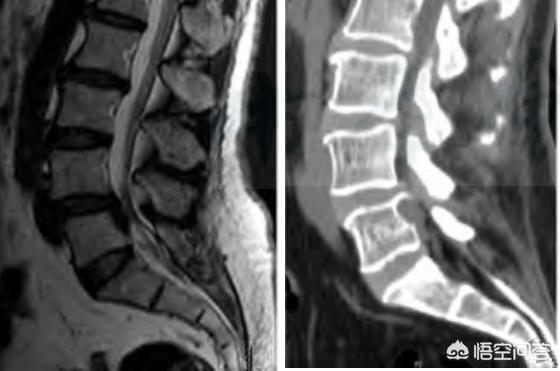

Die lumbale Spinalkanalstenose ist eine Erkrankung, bei der der lumbale Spinalkanal oder das Foramen intervertebrale verengt ist und die Cauda equina oder die Nervenwurzeln zusammendrückt. Die Hauptmanifestationen sind lumbale Rückenschmerzen und Ischiasbeschwerden, oft begleitet von Claudicatio intermittens. Ein zentraler Durchmesser des Wirbelkanals von ≤10 mm ist eine absolute Stenose, 10 bis 13 mm sind eine relative Stenose, und der vordere und hintere Durchmesser der Fossa saphena magna von 3 mm oder weniger sind Stenosen.

Relativ selten, aufgrund einer angeborenen Unterentwicklung des Wirbelkanals, die zu einer Verengung des Wirbelkanals führt, so dass der Spinalnerv oder der Nervus cauda equina, durch den der Wirbelkanal verläuft, gereizt und komprimiert wird, was zu einer Reihe von klinischen Symptomen führt. Die Hauptmerkmale sind: der zentrale Durchmesser des Wirbelkanals ist ≤10 mm, mehrere Wirbel sind betroffen, und das Verhältnis des sagittalen Durchmessers des cephalo-lateralen Randes der Wirbelplatte zum sagittalen Durchmesser des kaudalen Randes der Wirbelplatte ist >1 (normal ≤1).

Der Wirbelkanal ist eine knöcherne, faserige Röhre, die von den Foramina aller Wirbel gebildet wird und das Rückenmark, die Rückenmarkshaut und das Fettgewebe enthält. Er besteht aus dem Rücken der Wirbel, dem hinteren Rand der Bandscheiben und dem hinteren Längsband auf der Vorderseite, der Bogenplatte, dem Ligamentum flavum und den Synovialgelenken auf der Rückseite sowie den Wirbelwurzeln und den Zwischenwirbellöchern auf beiden Seiten, wobei die Nervenwurzeln aus den Zwischenwirbellöchern austreten. Der Wirbelkanal ist im vierten bis sechsten Brustwirbel am engsten, im Halswirbel 7 und im Lendenwirbel 4 am kleinsten. Die Spinalkanalstenose wird durch angeborene und erworbene Faktoren wie lumbale Bandscheibenvorfälle, Hyperplasie der Wirbelkörper, Spondylolisthesis und Hypertrophie des hinteren Längsbandes und des Ligamentum flavum verursacht.Kurz gesagt, Läsionen der angrenzenden Gewebestrukturen, die den Wirbelkanal umfassenSpinale Stenose, verursacht durch usw. Die Spinalkanalstenose tritt im zervikalen, thorakalen und lumbalen Segment auf, und die lumbale Spinalkanalstenose äußert sich beispielsweise klinisch als1. Schmerzen, Muskelschwäche, Schmerzen verschiedener Art, wie Wundheit, Taubheitsgefühl, Schwellung, ausflussartiger und brennender Schmerz; 2. Cauda-Equina-Kompression, Störungen des Stuhlgangs, Taubheitsgefühl im Dammbereich; 3. intermittierende Claudicatio (charakteristische Erscheinungen, die beim Gehen auftreten und sich nach dem Stehen oder Hocken und Ruhen bessern)